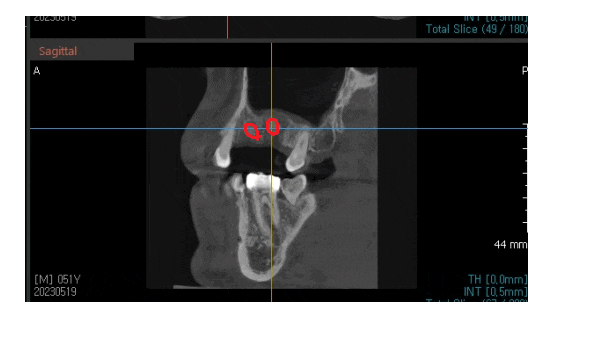

ct 사진을 찍어보았는데요.

주변 치아와 다르게

뼈가 쏙 들어간게 보이실겁니다.

잇몸 뼈를 다 갉아 먹었네요ㅠ

뭐가 있어야 임플란트를 심는데

도저히 심을 수 있는 뼈가 안보입니다.